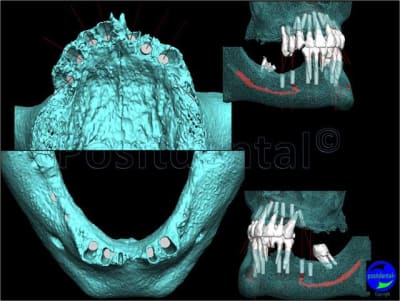

S.I.A.O

(simulation implantaire assistée par ordinateur)

C’est ton humble avis, un verre peut être à moitié vide ou à moitié plein, les outils fournis par positdental ont permis de réaliser le plan de traitement implantaire, faire une MICIPE bi-maxillaire en 1 seule intervention n’est pas courant.